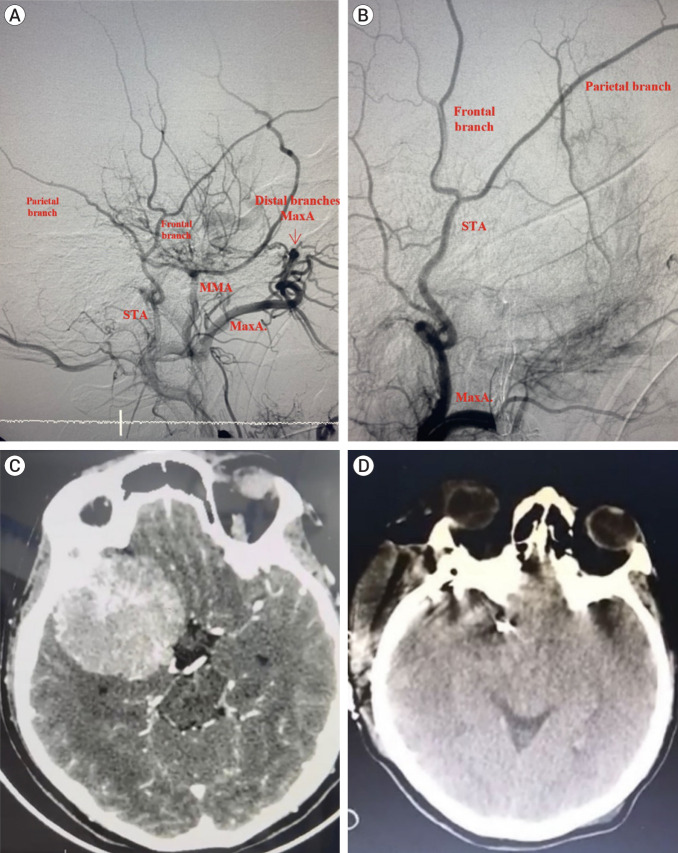

Methods: A literature review was conducted using PubMed, Scopus, and Web of Science databases with keywords related to preoperative embolization and highly vascularized tumors, detailing its definition, indications, diagnostic considerations, procedural aspects, clinical and surgical implications, and associated complications. The findings are supported by data from 309 patients with brain, head, and neck tumors treated with preoperative embolization at Hospital Clínica Kennedy in Guayaquil, Ecuador, from 2015 to 2023. Cases without embolization or those below the clavicular border were excluded. Illustrations and photographs, based on the authors' surgical experience, are included with informed consent.